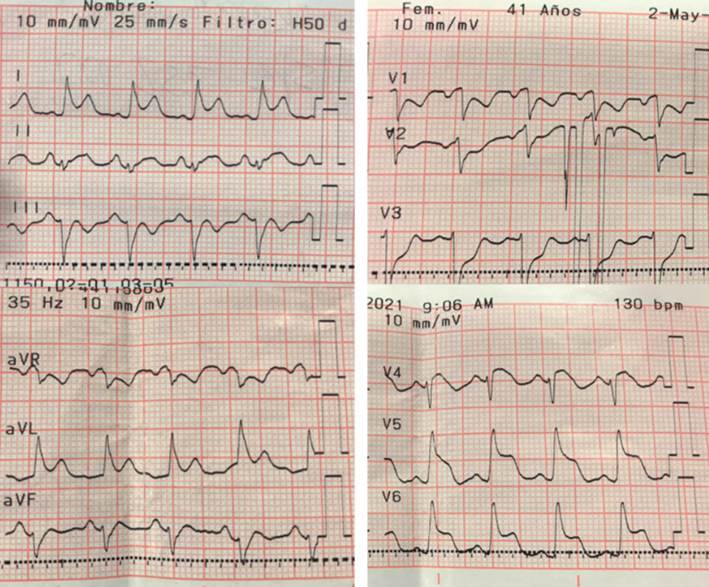

A las 24 horas de la CACG, presentó un nuevo episodio de dolor torácico. Al examen físico, se destacaba polipnea, taquicardia de 130 ciclos por minuto, PA 180/110 mmHg y estertores crepitantes en bases de ambos campos pulmonares. Se realizó nuevo ECG que presentó taquicardia sinusal, agregando supradesnivel del segmento ST en DI, avL y de V4 a V6 (figura 4).

Los hallazgos electrocardiográficos más frecuentes son la taquicardia sinusal y alteraciones inespecíficas del segmento ST y la onda T, así como anormalidades de la conducción y arritmias. En el ecocardiograma puede aparecer disfunción sistólica global o regional y derrame pericárdico. La miocarditis fulminante a menudo se presenta como miocardio engrosado e hipocontráctil, como resultado del edema intersticial y la pérdida de contracción ventricular4.